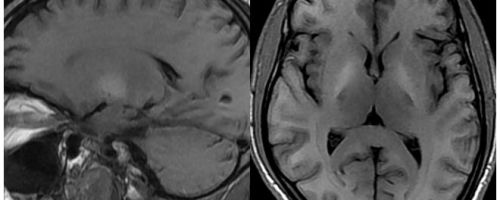

Влияние алкоголя на мозг не пьющего человека, значительно ниже, чем на человека часто находящегося в состоянии опьянения.